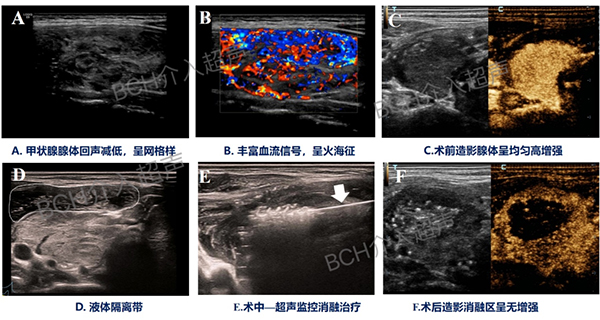

3)全过程管理,术前超声及造影可准确评估病变严重程度,规划消融范围,术中实时监控,术后超声及造影准确评估消融范围,评价治疗效果;